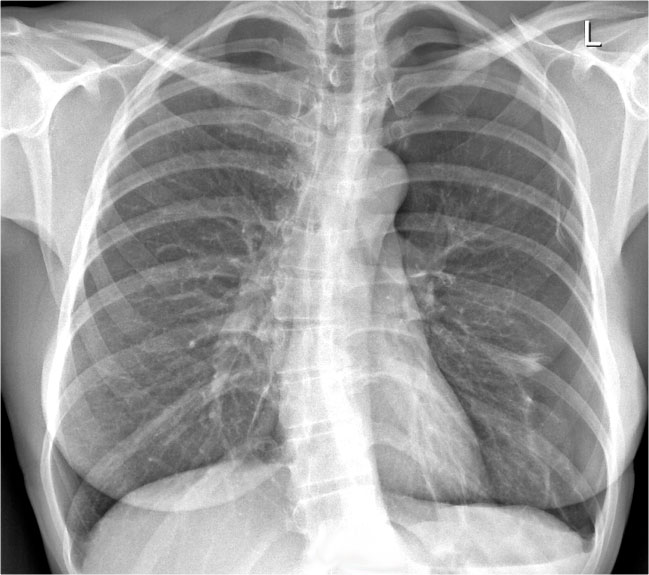

Case Example: Subtle Signs of Congestive Heart Failure

Begin by reviewing these current chest radiographs.

Based solely on these images, one might suspect congestive heart failure (CHF), though the findings are subtle.

Now review the previous study…

Scrolling between the current and prior films significantly increases diagnostic confidence in your diagnosis of congestive heart failure.

Key comparative findings include:

• Cardiac size: Slightly increased compared to the previous study; however, cardiomegaly was already present.

• Pulmonary vasculature: Mild vascular engorgement suggesting elevated pulmonary venous pressure.

• Interstitial markings: Subtle signs of interstitial edema .

• Pleural effusions: Bilateral small effusions, with subtle changes in the inferoposterior borders of the lower lobes, suggesting fluid accumulation.